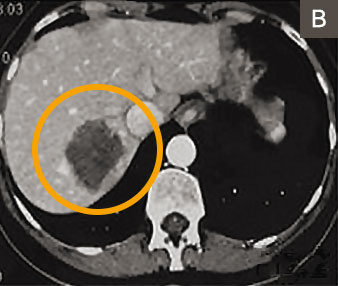

Alternativ oder ergänzend zur Leberteilentfernung können Lebertumoren auch mit einer Nadeltechnik 2 verödet werden. Dabei erzeugen Radiofrequenzen oder Mikrowellen hohe örtliche Hitze. Die Methode ist für nicht oberflächlich gelegene Lebertumoren bis zu einer Grösse von drei Zentimetern geeignet (Abbildungen A – C). Sie wurde vom Autor und seinem Team seit 15 Jahren angewandt und weiterentwickelt 3 und bietet folgende Vorteile: Es geht weniger normales Lebergewebe verloren als bei der Leberteilentfernung und der Eingriff kann ohne Bauchschnitt durchgeführt werden. Entsprechend ist die Nadeltechnik für die Patienten wenig belastend.

1 Woche nach Nadelbehandlung: Verödetes Leberareal (dunkelgrauer Fleck, etwas grösser als Metastase)